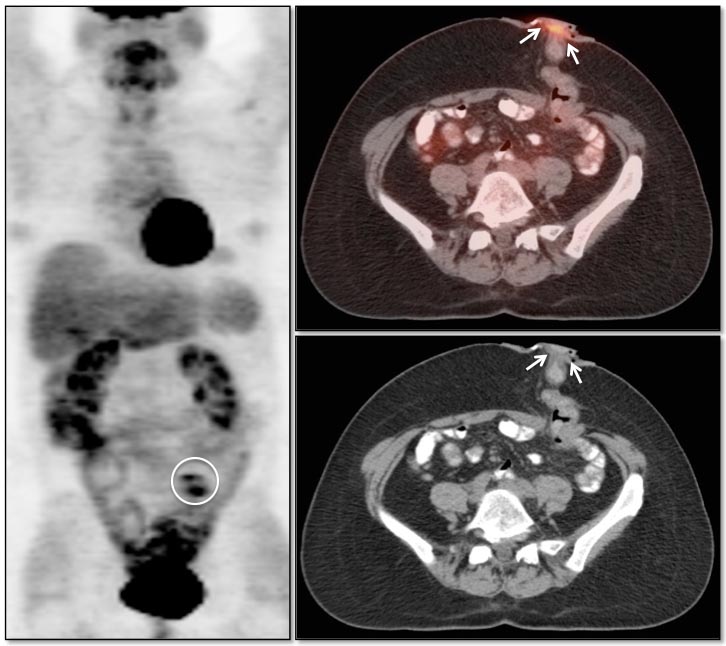

Generally, colonic uptake should be considered normal unless:

• There is an accompanying CT abnormality (e.g. focal bowel wall thickening or focal mass); or

• A solitary focus of intense uptake presents in an otherwise non-avid (or minimally avid) colon.  Although this focal uptake may still represent normal physiologic uptake, it is reasonable to raise the possibility of a small polyp and recommend colonoscopy (polyps are rarely visible on the CT images).